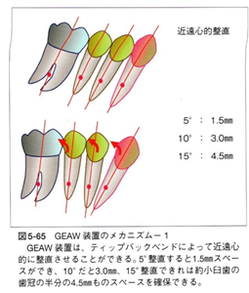

その為に MEAW(マルチループ)を利用して 歯を立体的に動かしています。

臼歯部が何らかの理由で近心部の歯を押し出していくメカニズムは上下ほぼ同じです。

下の図は歯の押し出しが前歯まで影響を与えている症例です。

大臼歯部が近心に傾いて咬み合わせの高さが低くなるとその歪みが前歯に伝わり、前突状態となります。

MEAW(マルチループ)を利用して歯を動かす隙間の作り方は2種類あります。

②ふたつ目は以下の様な原理です。

①では歯が近心側に綺麗に傾いた場合ですが、歯が内側(舌側)に傾く事もあります。

この場合もMEAW(マルチループ)によって内側(舌側)に傾むいた歯を起こしていきます。

その為にMEAW(マルチループ)を利用して歯を立体的に動かしています。

MEAW(マルチループ)を利用して歯を動かす隙間の作り方は2種類あります。

①ひとつ目は以下の様な原理です。

これを身近な7冊の本を使って説明していきましょう。